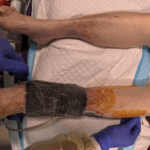

Enrolled Nurse (EN): Permitted Procedures

This page provides a quick reference of Care Plans and Tutorials available on The Wound Sandwich (TWS) which are permitted to be undertaken by staff with a Enrolled Nurse (EN) qualification. Additional applicable qualifications are also listed.